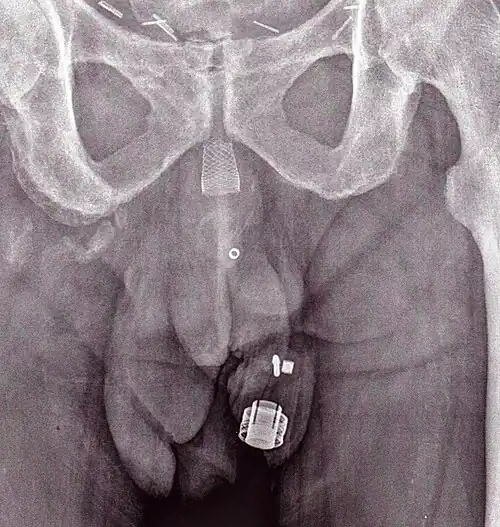

Uma imagem de raio X de um ZSI 375 implantado. O aparelho está desativado - a mole está comprimida abaixo do topo do cilinder. O paciente está continente. -